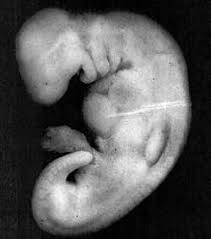

(Prof. Keith Moore). Lalu ia bergegas menuju ke ruang laboratoriumnya, meneliti tahap awal perkembangan embrio dengan menggunakan sebuah perangkat teknologi mikroskop. Kemudian beliau membandingakan dengan apa yang terlihat melalui mikroskop dengan gambar foto seekor lintah.

Dan beliau sangat terkaget-kaget ketika beliau menyaksikan kemiripan atara keduanya (embrio manusia dan gambar lintah). Setelah sekitar delapan puluh pertanyaan diajukan kepada Prof. Keith Moore, akhirnya beliau mengatakan, “

Alaqa berarti ‘sesuatu yang tampak seperti seekor lintah’ pada tahap-tahap awal, embrio itu tampak seperti seekor lintah. Selain memang ia tampak seperti seekor lintah, dia juga menerima pasokan (menghisap) darah dari sang ibu.

Alaqa berarti ‘segumpal darah’. Karena pada jaman sekarang ini, dengan adanya banyak pakar termasuk Prof. Keith Moore mengatakan, Bahwa pada tahap perkembangan sebuah embrio disamping tampak seperti seekor lintah, juga tampak seperti segumpal darah, karena pada tahap-tahap awal perkembangan ‘alaqa’ yakni pada masa tiga atau empat pekan, segumpal darah itu akan terbungkus dengan serat-serat pembuluh. Dan selama pekan ketiga dari perkembangan awal embrio tersebut, sirkulasi darah belum terjadi, itu baru terjadi pada tahap berikutnya. Oleh karena itu tampak seperti segumpal darah. Jika anda perhatikan ringkasannya, setelah dilakukan pengguguran kandungan, anda bisa saksikan bahwa ‘alaqa’ itu tampak seperti segumpal darah.